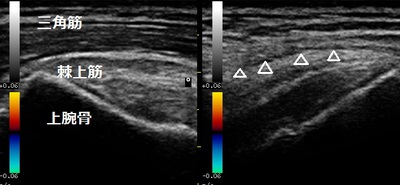

右肩患部 左正常側

右腕を前方や側方から肩の高さまで上げようとしても痛くて自力で腕の重みを支えられません。

超音波画像では患部のperibursal fatが落ち込んでいて断裂を示唆していました(画像⇩矢印)。また、筋肉の厚みも正常側と比較して減少していました(画像↕矢印)。

右腕を挙げようとすると首から肩などに痛みがひどく出るので疼痛改善する施術やマッサージを行います。日常生活では断裂の拡大を防ぐために力仕事や球技などのスポーツ、筋力トレーニングを休止します。